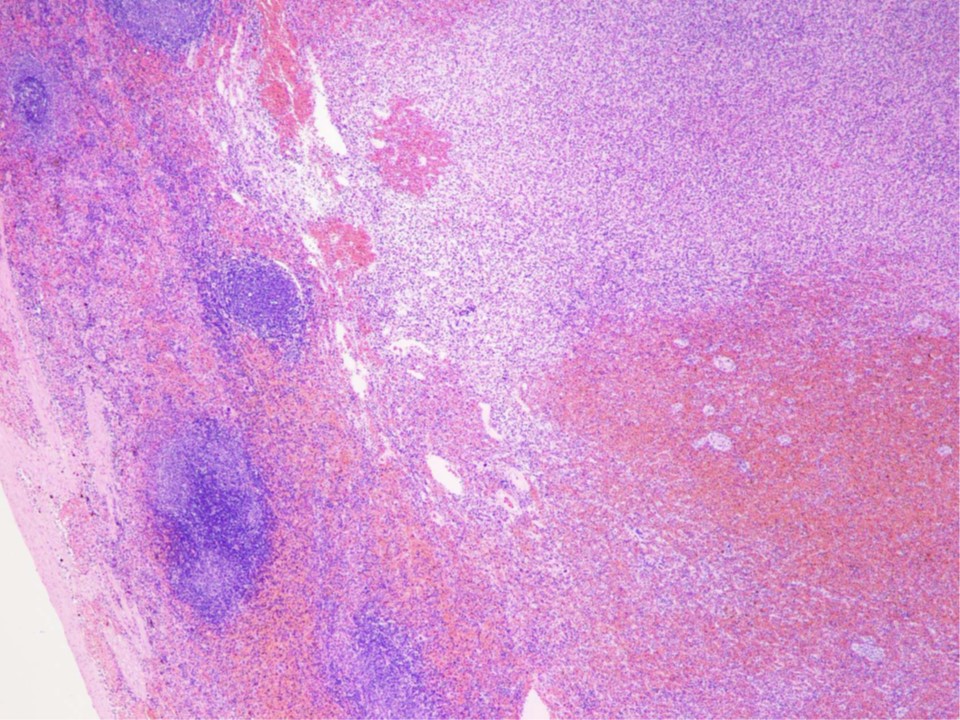

▲病理結果:リンパ濾胞様組織の過形成性増殖巣から形成され、腫瘤内の赤脾髄は血液の貯留や髄外造血により中度に拡張している。腫瘍性増殖を示す細胞や、感染性病原体は認めない。